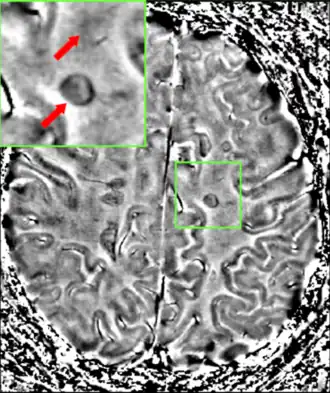

• Lesions – A classic method in which a brain-region of interest is naturally or intentionally destroyed to observe any resulting changes such as degraded or enhanced performance on some behavioral measure. Lesions can be placed with relatively high accuracy "Thanks to a variety of brain 'atlases' which provide a map of brain regions in 3-dimensional" stereotactic coordinates.

The part of the picture emphasized shows the lesion in the brain. This type of lesion can be removed through surgery.